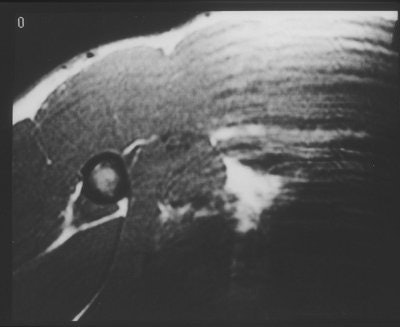

| The SE T1-weighted image [TR/TE (ms) 616/11] at the same level as figure above does not clearly show the ruptured site. This was thought to be due to the gap being filled with a hematoma having a similar signal intensity as the muscle. Images courtesy of Dr. Kenjirou Ohashi, department of radiology, University of Iowa College of Medicine; reprinted with permission from Skeletal Radiology, October 1996, Vol. 25:7, pp. 625-628. |